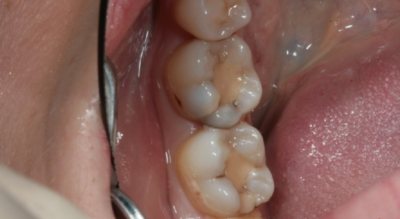

Диагностику заболевания врач стоматолог проводит с помощью основных и дополнительных методов исследования. В первую очередь проводится осмотр больного зуба. Если возле пломбы образуется полость или через эмаль просвечивает кариозный процесс, этих признаков будет достаточно для определения заболевания. Также специалист собирает анамнез болезни, спрашивает о первичном лечении.

Если стоматолог увидит, что пломба изменила цвет, но не сможет сразу определить кариес, он назначит рентгенологический снимок. Рентген также понадобится в случае, если вторичный кариес возник в депульпированном зубе.

С помощью рентгена можно оценить глубину и локализацию кариозного разрушения. На снимке пломба будет выглядеть как белое пятно, а кариес – как темное.

- вначале образуется микротрещина между контактными поверхностями зубной эмали и композитного материала;

- через щель проникает слюна вместе с ферментами, бактериями и другими компонентами;

- бактерии (Streptococcus mutans) активно размножаются, продуцируя органические кислоты, которые разрушают костную ткань зуба, образуя глубокий кариес.

Процесс колонизации бактерий и негативного влияния кислот, выделяемых микроорганизмами, на зубную структуру провоцируют отторжение полимерного материала от стенок зуба.